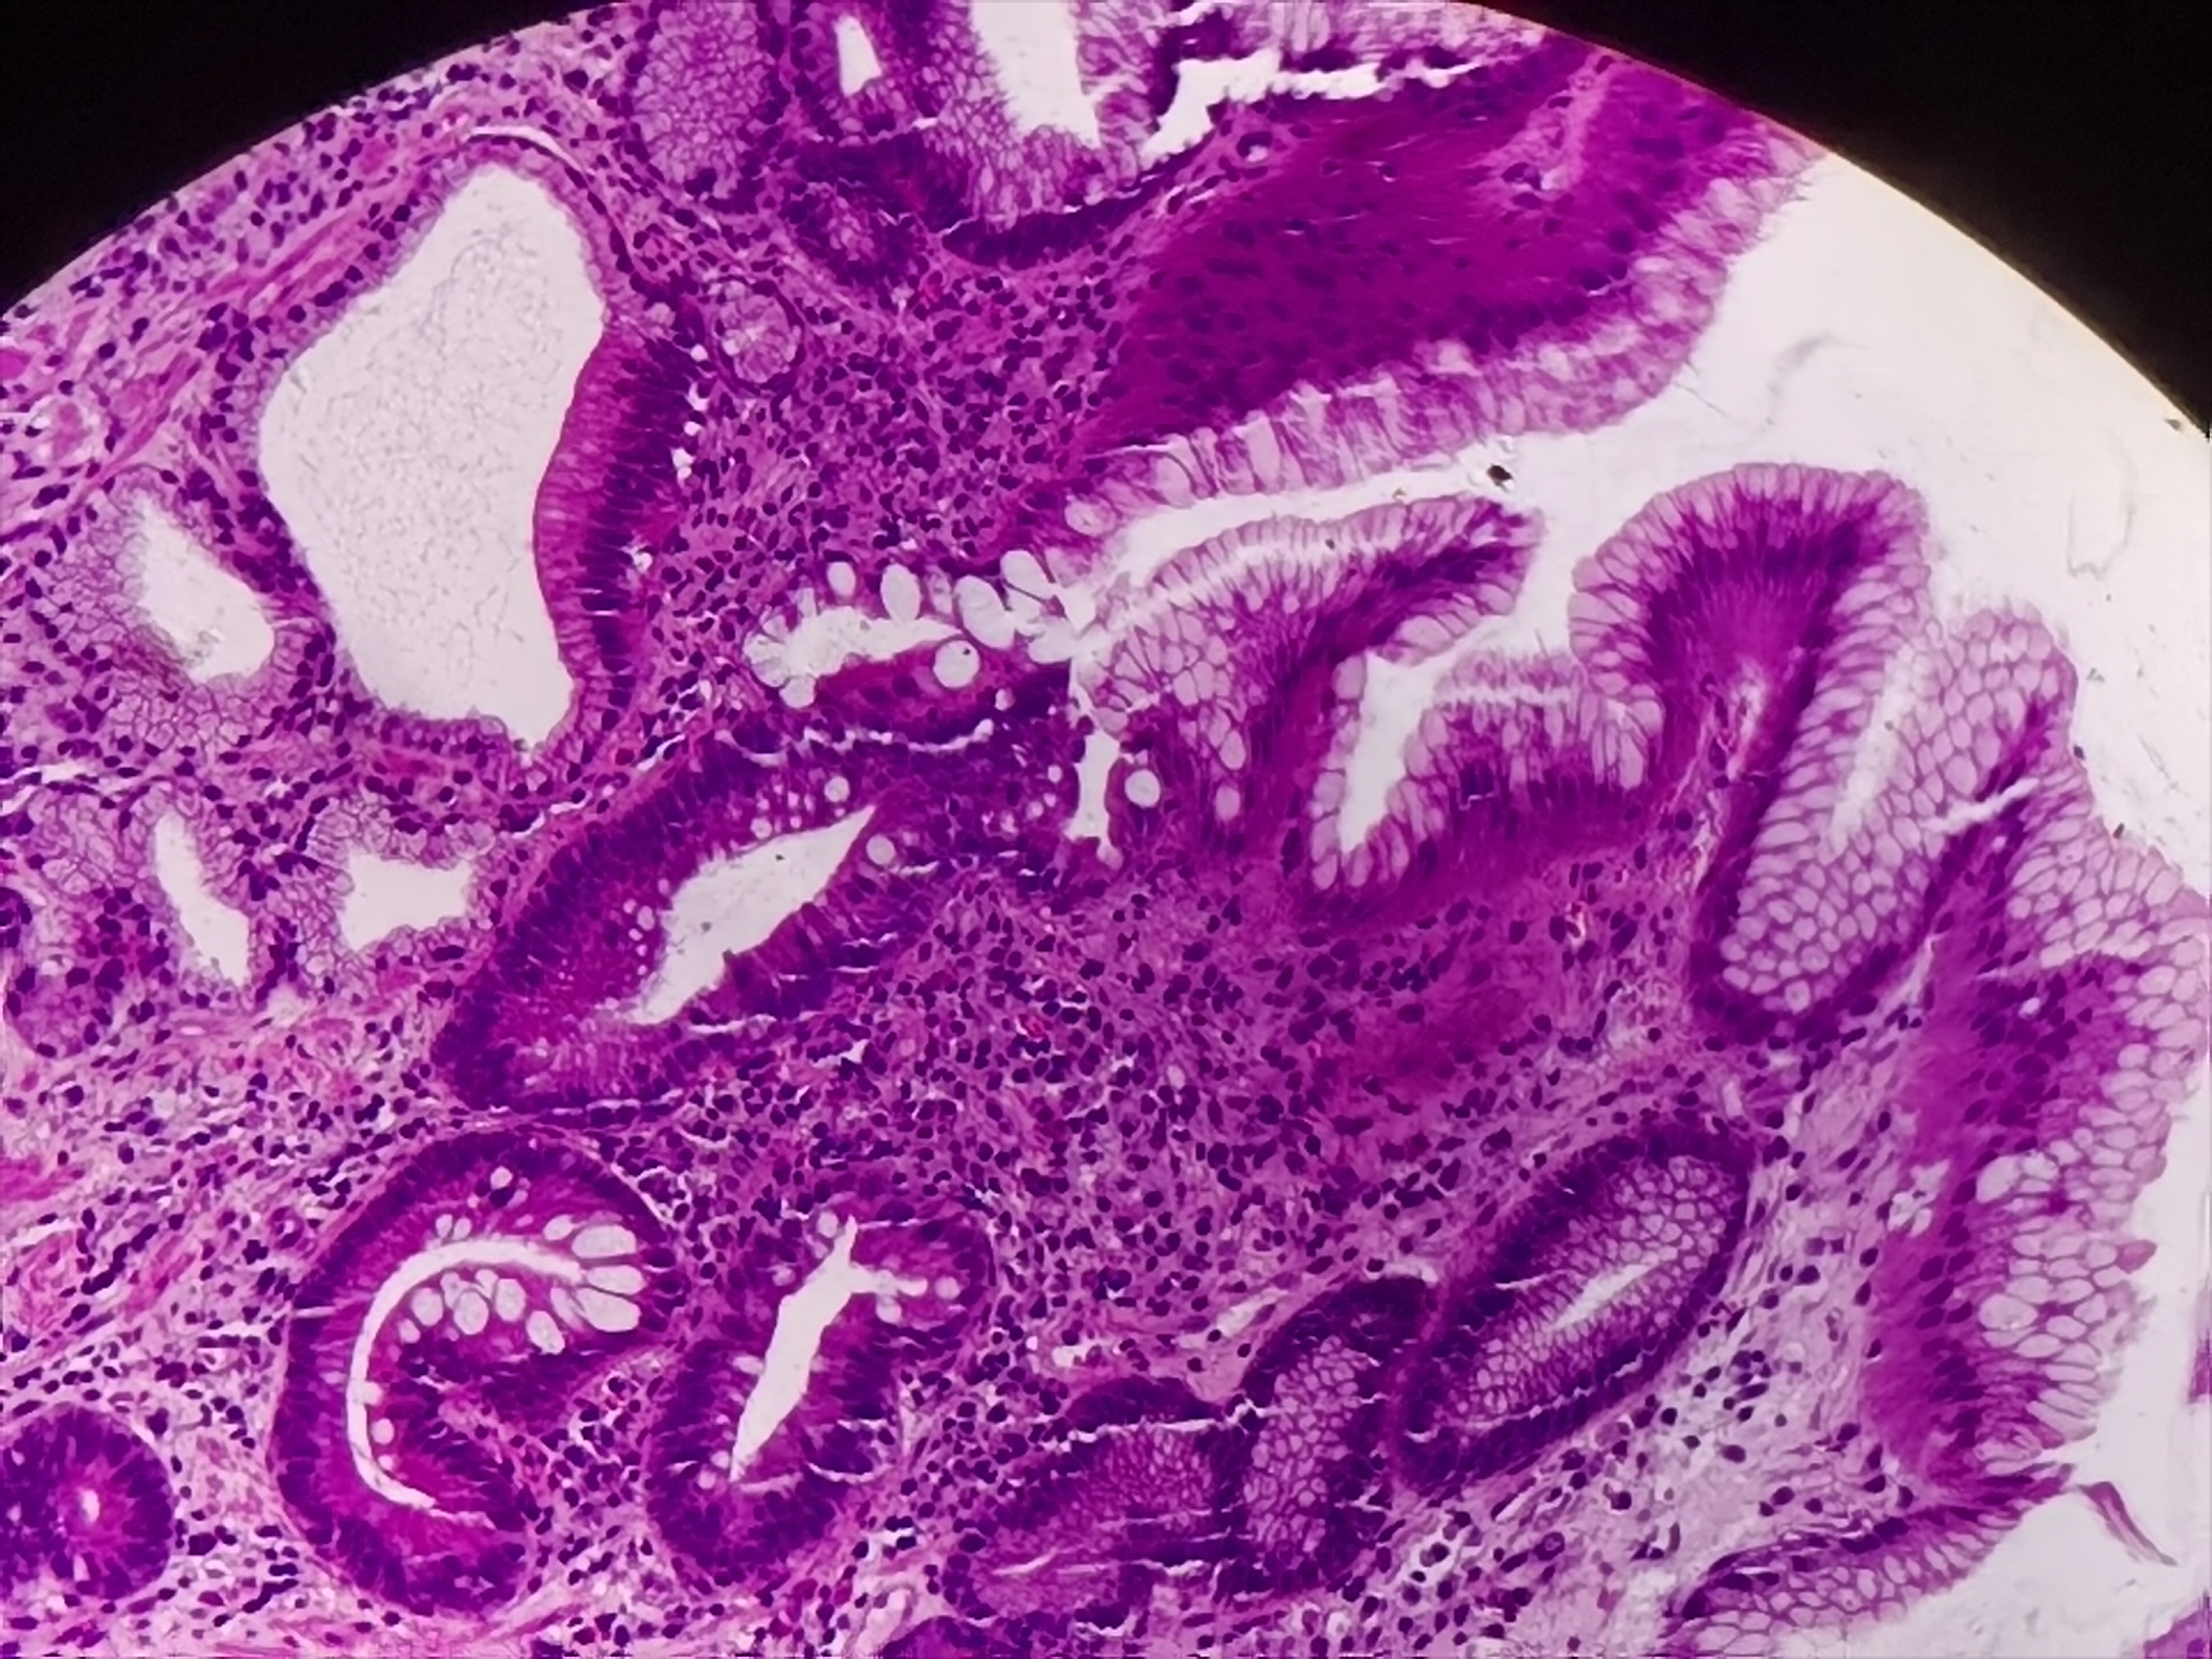

胃体活检

性别

男

年龄

57岁

临床诊断

胃多发溃疡

一般病史

胃体可见多枚点状溃疡

标本名称

胃体粘膜活检

大体所见

灰白灰红组织2块

图1

符合溃疡,HP?